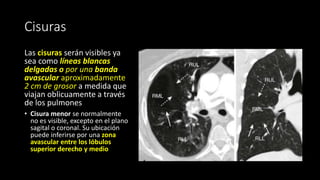

Cisuras

Las cisuras serán visibles ya

sea como líneas blancas

delgadas o por una banda

avascular aproximadamente

2 cm de grosor a medida que

viajan oblicuamente a través

de los pulmones

• Cisura menor se normalmente

no es visible, excepto en el plano

sagital o coronal. Su ubicación

puede inferirse por una zona

avascular entre los lóbulos

superior derecho y medio